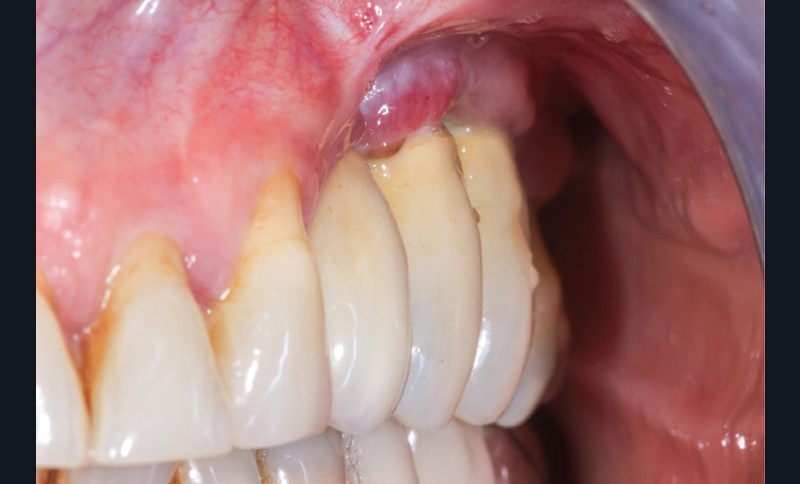

Le projet prothétique pré-implantaire [11] est également l’une des clés du succès ; il doit permettre un positionnement tridimensionnel optimal de l’implant, notamment avec un environnement tissulaire adéquat ; selon la littérature, 2 mm de tissu kératinisé sont nécessaires autour des implants pour fonctionner comme un bouclier autour de lui [12] (fig. 3).